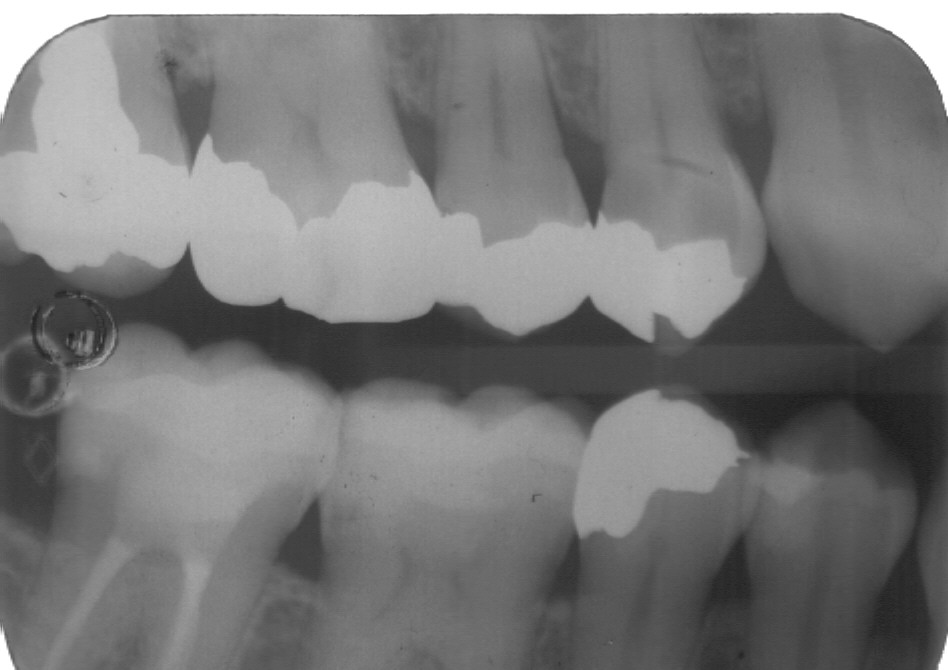

Nel nostro Studio impieghiamo un sistema radiografico computerizzato, il Vista Scan Plus della Dürr che consente di ottenere immagini di alta qualità (vedi confronto analogico/digitale) con dosi radiogene sensibilmente più basse per il paziente.

Con Vistascan Plus siamo in grado di ottenere, nel giro di pochi minuti, tutte le immagini che ci servono per un corretto ausilio diagnostico: bitewing, endorali, ortopantomografie, teleradiografie.